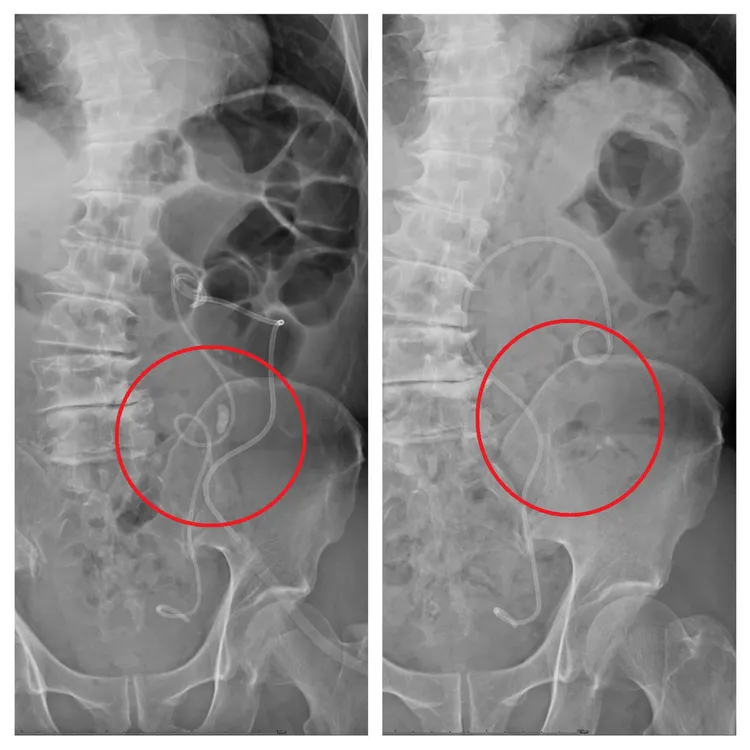

患者輸尿管卡了1顆1.8公分的結石。院方提供